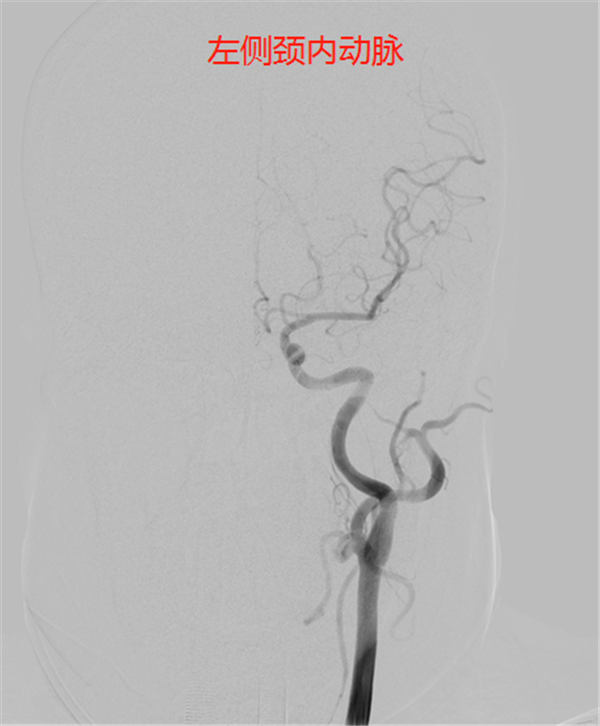

后对全脑血管进行造影,显示——